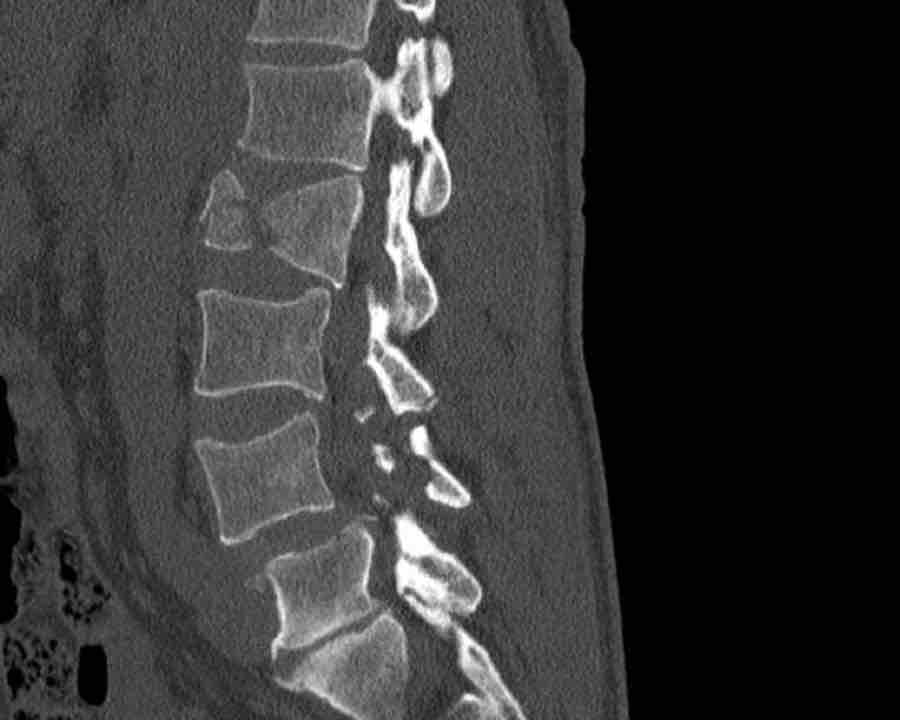

A3 Incomplete Burst fractures

Fracture with any involvement of the posterior wall; only a single endplate fractured.

A vertical fracture of the lamina is usually present and does not constitute a tension band failure.

What is the AO-type of the vertebral body fracture based on only these two inages?

Findings:

- Fractures of the vertebral body with involvement of upper endplates (1 points) and posterior wall (2 points)

- Bulging of the posterior wall without any other signs of dislocation is the result of the burst fracture.

Therefore no C injury.

Conclusion

Injury type A3

- No C or B injury

- Fractures vertebral body with involvement of upper endplate (1 point) and posterior wall (2 points)